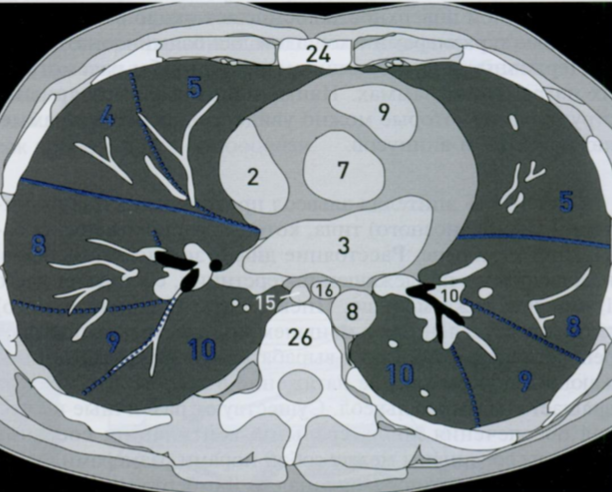

КТ грудной клетки №2

Назовите все анатомические структуры, которые Вы знаете, на данном КТ срезе (9).

Найдите грудные позвонки. Затем верхнюю полую вену, восходящую и нисходящую аорту, легочный ствол с легочными артериями, бифуркацию трахеи, непарную вену и пищевод.

A

1 - верхняя полая вена

7 - восходящая аорта

8 - нисходящая аорта

9 - легочный ствол с правой легочной артерией (а) и левой легочной артерией (b)

10 - сосуды

81b - бифуркация

15 - непарная вена

16 - пищевод

Синим цветом отмечены номера сегментов.